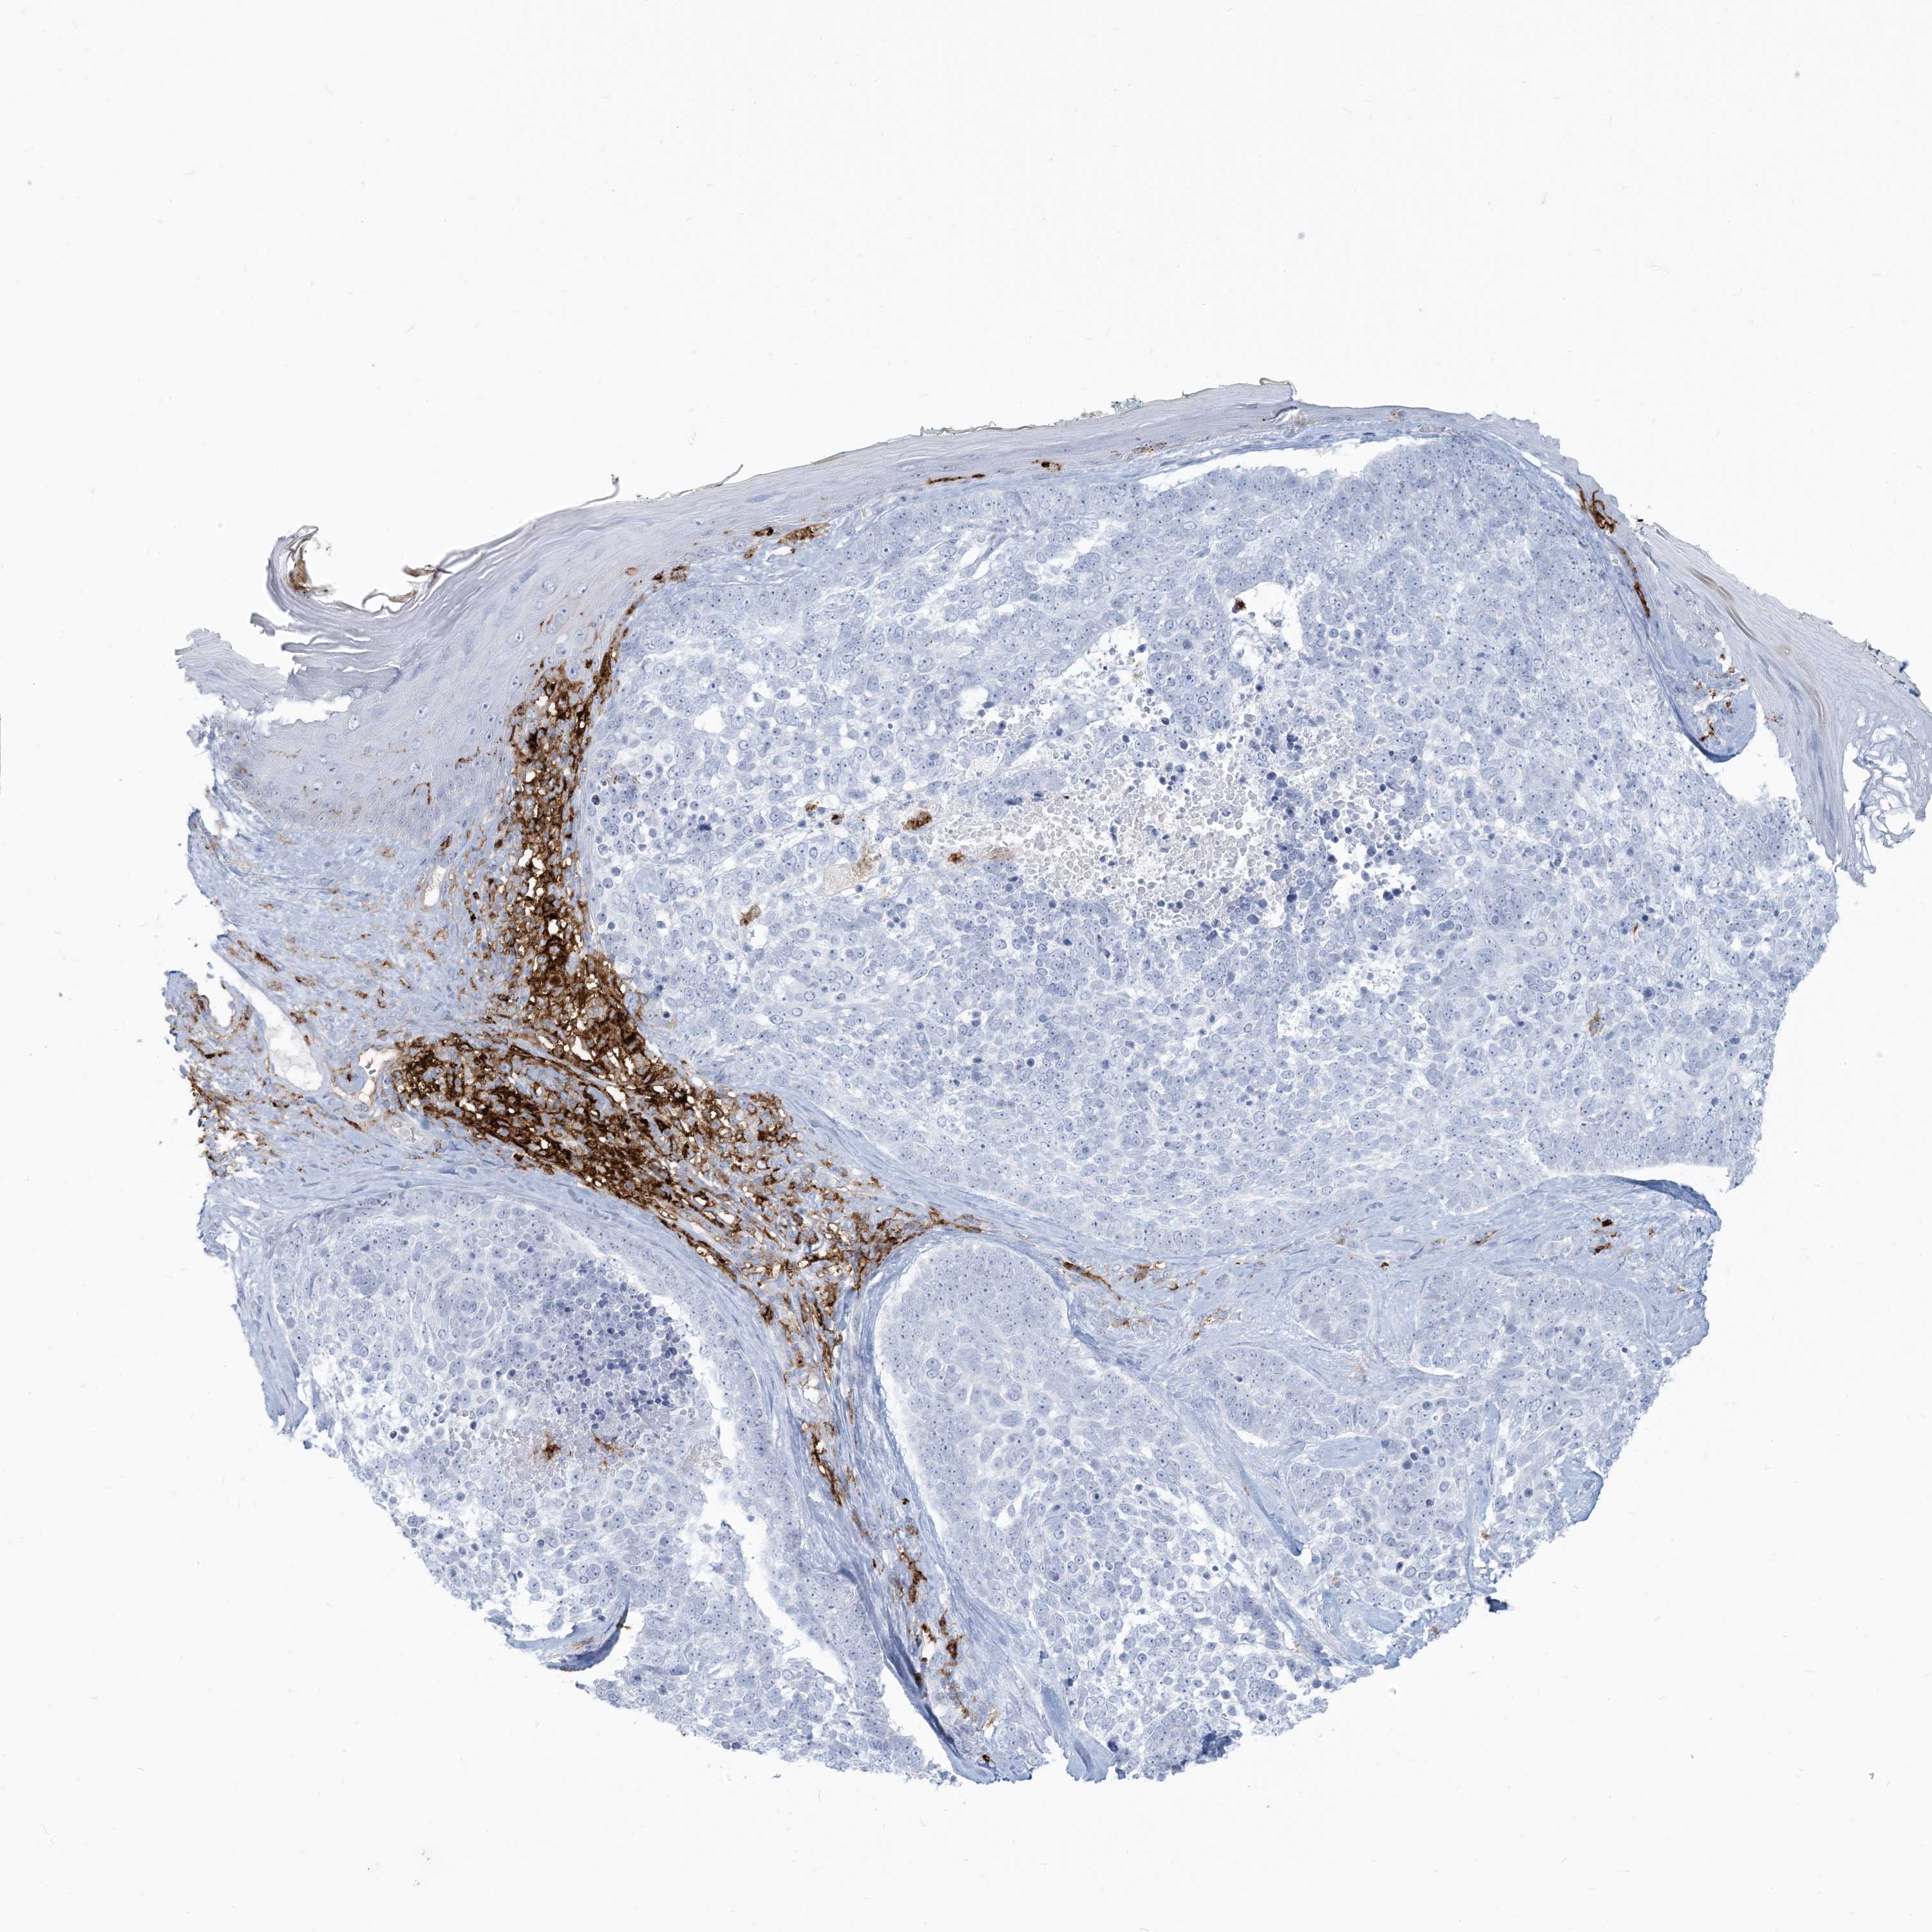

SKIN CANCER - Protein expressioni

A mouse-over function shows sample information and annotation data. Click on an image to view it in a full screen mode. Samples can be filtered based on level of antibody staining by selecting one or several of the following categories: high, medium, low and not detected. The assay and annotation is described here.

Antibody stainingi

Antibody staining in the annotated cell types in the current human tissue is reported as not detected, low, medium, or high, based on conventional immunohistochemistry profiling in selected tissues. This score is based on the combination of the staining intensity and fraction of stained cells.

Each image is clickable and will lead to virtual microscopy that enables deeper exploration of all samples and also displays staining intensity scores, fraction scores and subcellular localization as well as patient and tissue information for each sample.

Antibody CAB015400

Basal cell carcinoma

Squamous cell carcinoma, NOS

Squamous cell carcinoma, metastatic, NOS

Squamous cell carcinoma in situ, NOS

Adnexal tumor, benign